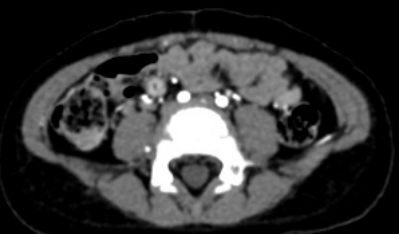

因是同行介绍过来的,儿中心普外科梅医生通过电话提前了解了相关情况,虽暂无影像学依据支持,但从患儿反复无痛性血便、贫血联想到 小儿外科比较熟悉的疾病—梅克尔憩室(Meckel’s diverticulum)。入院以后,为了明确诊断,患儿再次接受了B超、腹部增强CT和 99m锝同位素扫描的检查,虽然腹部B超报告未见异常,但腹部增强CT显示右下腹局部肠壁密度增高,进一步行同位素扫描可见右下腹放射性浓聚灶。作为主治医生,起初的怀疑终于找到了影像学的依据!

· 影像学检查 ·

右侧髂血管前方局部肠段密度增高

右侧髂血管内侧局部放射性浓聚灶